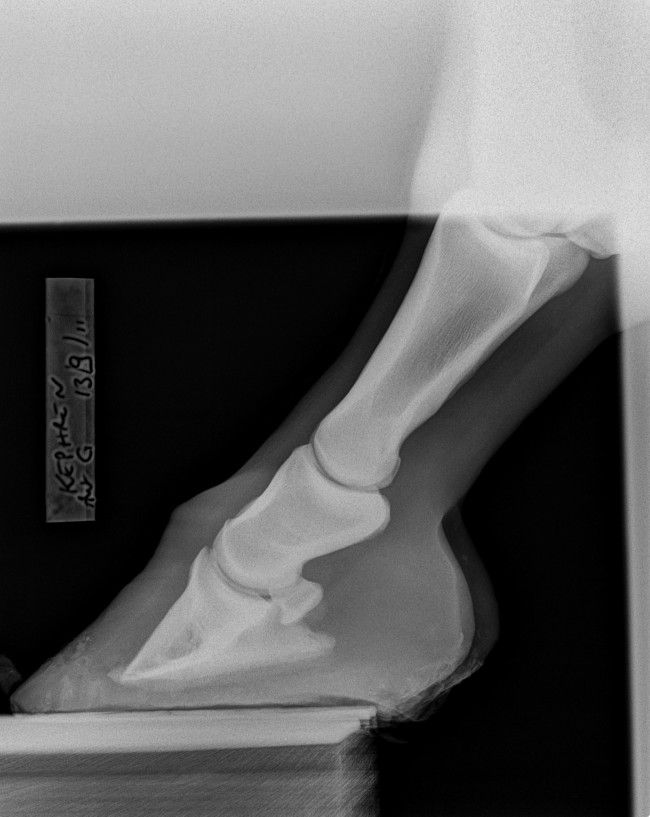

| Dire merci | Bonsoir, titre pas très explicite je vous l'accorde ! Je vais essayer de faire court. J'avais fais un post sur les souci de fourbure de Kephren (bascule P3 help). Mais je réexplique : PS de 10 ans arrivé fourbu il y a 3 ans et demi. Ferré avec toutes sortes de fers sans succès. Plusieurs tentatives pieds nus mais il souffrait trop. Finalement re déferré en juin 2013 car les fers ne tenaient plus que 3 jours, tout le pied était arraché par les déferrages intempestifs, et la résine lui provoquait une inflammation et une nouvelle crise. Bref, donc pieds nus depuis 8 mois, aidé de chaussons 24h/24 pendant 4 mois, puis étant dans la boue, sans rien. Visuellement il semble que nous ayons bien rattrapé la bascule de la phalange, Kephren marche à présent pieds nus, mais encore très sensible sur terrain irrégulier. Depuis environ 2 mois son antérieur gauche est chaud de temps en temps dans ces moments la, il n'est pas à l'aise. Avant hier je décide de refaire des radios pour voir ou on en est : Verdict du véto : la bascule est en bonne voie, bien rattrapée, mais la phalange est très abimée, nécrosée, elle est bouffée !!! Le véto a perdu les premières radios de 2011, donc ne peut pas comparer J'ai essayé de lui demander plus d'explications mais je n'ai pas pu en avoir ... Sachant qu'il y a 3 ans il m'a dit : c'est foutu y a rien à faire on peut pas rattraper la bascule... et sachant que finalement je suis en train de prouver le contraire, j'attends d'autres avis, j'ai moyennement confiance ... J'ai envoyé les radios par mail à la clinique véto de Gironde, on m'a répondu qu'on pouvait, à force de parage adapté, redresser un les aplombs et la phalange mais que ce sera long... merci mais c'est déjà ce qu'on fait depuis 8 mois, ça répond pas à ma question, la phalange est bouffée oui ou non ? Et si oui pourquoi et que peut on faire ?? toujours pas eu de réponse ![]() Qu'en pensez vous ?? Merci ! Voici les radios de 2011 : [url=https://www.1cheval.com/membre/services/photos/images/103924.jpg] ![]() [/url] [url=https://www.1cheval.com/membre/services/photos/images/103925.jpg] ![]() [/url] et voici celles d avant hier : [url=https://www.1cheval.com/membre/services/photos/images/175921.jpg] ![]() [/url] [url=https://www.1cheval.com/membre/services/photos/images/175922.jpg] ![]() [/url] |

DéconnectéDire merci | Sur la radio de 2011, on voit déjà que le bord solaire de P3 est irrégulier, voir possiblement fracturé sur le côté droit. Je ne vois pas de bascule plus que cela de P3. Dommage qu'il n'y ait pas de nouvelle vue récente du bord solaire. Sur les deux autres radiographies récente, on voit un remaniement osseux de la pinte de P3 et ce qui pourrait être une plus forte perte osseuse du bord solaire que sur les radios de 2011 – mais il faudrait une vue "bord solaire" récente pour confirmer ou infirmer. Mais surtout, ce qui me saute aux yeux sur la radios récentes, c'est 1/ P2 parallèle au sol (ce qui contribue à endommager encore plus P3 2/ le mauvais alignement des phalanges (alors qu'il était quasi correct en 2011), avec un axe pied-pâturon brisé vers l'arrière. |

DéconnectéDire merci | En premier lieu, et avec mes excuses, c'est P3 parallèle au sol que je voulais écrire. Oui, les phalanges étaient mieux alignées en 2011. Peut-être que le cheval marche mieux et que son sabot ressemble à quelque chose (photo ?), mais une chose est indéniable, P3 s'est détériorée depuis 2011. |

DéconnectéDire merci | Sur les radios de 2011, il n'y a pas de bascule de P3. Juste une pince fuyante, et encore, seulement sur la moitié basse de la paroi. Il est su et connu que maintenir P3 parallèle au sol, en ratiboisant les talons, engendre à moyen terme une détérioration du bord solaire de P3. En plus de désaxer les phalanges. C'est relativement simple à comprendre : lorsque P3 est parallèle au sol, les cartilages ungulaires n'ont plus de rôle à jouer, donc ils ne peuvent plus amortir en se distordant, et on se retrouve, du point de vue de P3, dans un cas similaire à celui d'une voiture qui "talonne", c'est-à-dire que c'est la structure osseuses qui encaisse directement les forces de réaction du sol. Quand on fait en sorte que P3 fasse un angle de 5-6° avec le sol, comme c'est communément admis que cela doit être (et comme l'a confirmée l'étude menée en Australie sur les Brumbies), l'arche constituée par P3+cartilage a une capacité de se déformer (de s'écraser) du fait des qualités mécaniques des cartilages ungulaires (qui peuvent se déformer et cherchent toujours à reprendre leur forme originelle – s'il n'y a pas maladie genre fourbure). Morale de tout ceci : maintenir volontairement P3 parallèle au sol dans la durée engendre des dégâts à P3 (et aussi, par répercussions, des troubles ostéopathiques "plus haut" . |